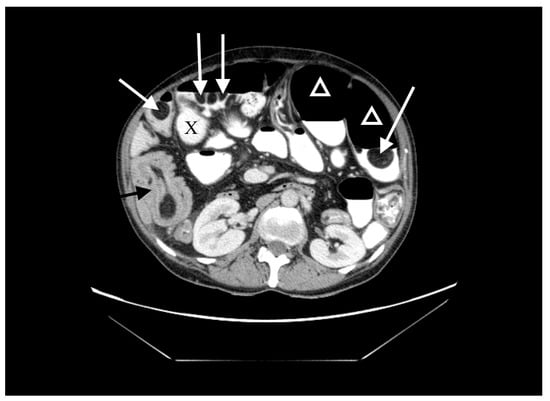

A 60-year-old woman was admitted to the emergency department complaining of acute abdominal pain, vomiting and diarrhea. Her medical history included appendectomy in childhood, hysterectomy, hepatic steatosis, chronic kidney disease (CKD) and chronic malnutrition with iron deficiency. She has also been treated for indeterminate inflammatory bowel disease (she reported taking sulfasalazine, 1.0 g three times daily) and had a twenty-year history of recurrent abdominal pain accompanied by a feeling of fullness and abdominal distension. Twenty-six years prior to admission, she underwent surgery for ileus and a large polyp in the ileum was locally resected. The patient did not provide documentation from her previous hospitalizations in other wards. Physical examination revealed absence of bowel sounds and generalized abdominal tenderness. Laboratory tests showed mild anemia and low serum protein level. Abdominal CT scan demonstrated small bowel distension (Figure 1) with ileo-ileal intussusception caused by one of multiple pedunculated lipomatous polyps arising from the mesenteric border of the jejunum (Figure 1 and Figure 2). Multiple giant diverticula were also visualized (Figure 1 and Figure 3).

Figure 1.

Contrast-enhanced computed tomography (CT) image of the abdomen, axial section. Multiple jejunal lipomas (white arrows), distended jejunum (triangles), one of the diverticula (X) and intussuscepted jejunum with a lipoma as the leading point (black arrow).